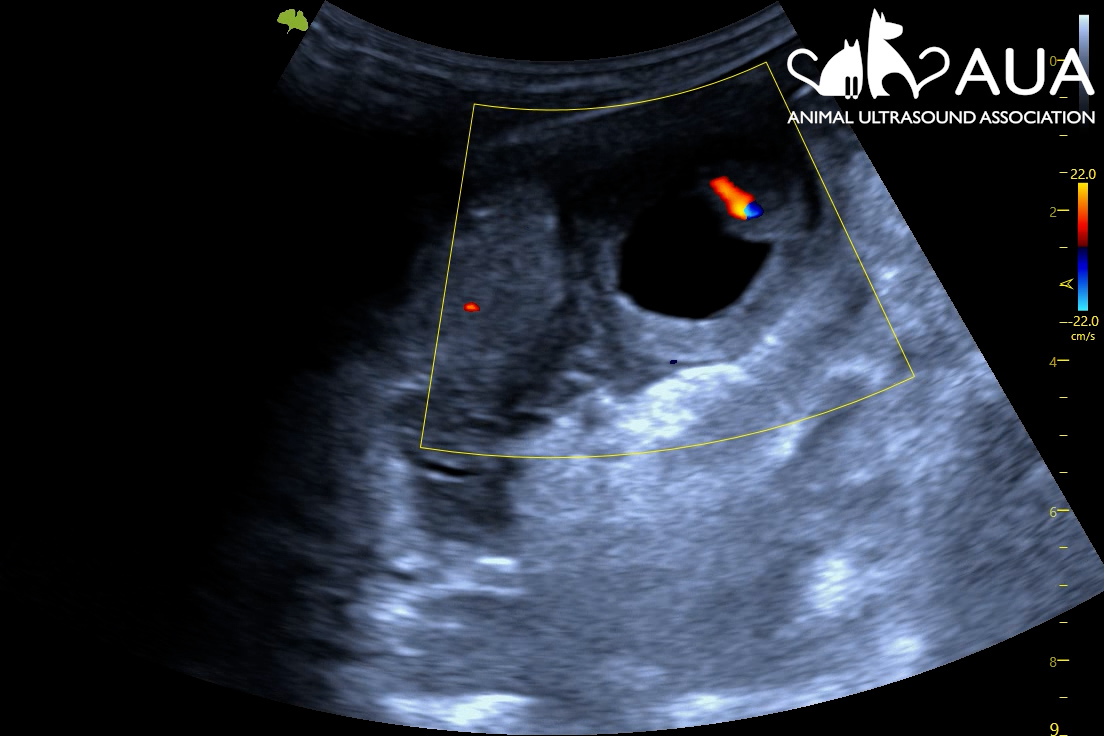

We confirmed 8 pregnancies today in Maidstone, Kent. Most of them were between 50 – 70 days, and it is surprising how tiny the foetus still is even at that stage of gestation. A human foetus at the same gestational age is about 8x larger; a feline fetus, 14x larger! Hence, when scanning you find yourself searching for a pea-sized foetus in a relatively large animal with a large, fluid-filled uterus. This involves moving your transducer along the uterine horns, and fanning back and forth, to try to spot a hiding future cria. At times, this is easier said than done, as alpacas are not always the most still and cooperative when having their abdomens touched.